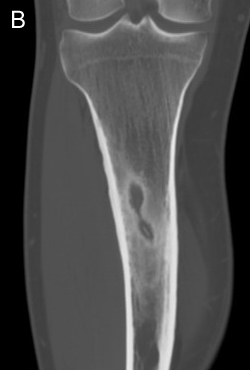

Most common site for stress fracture?

Metatarsals. Also common are calcaneus and tibia